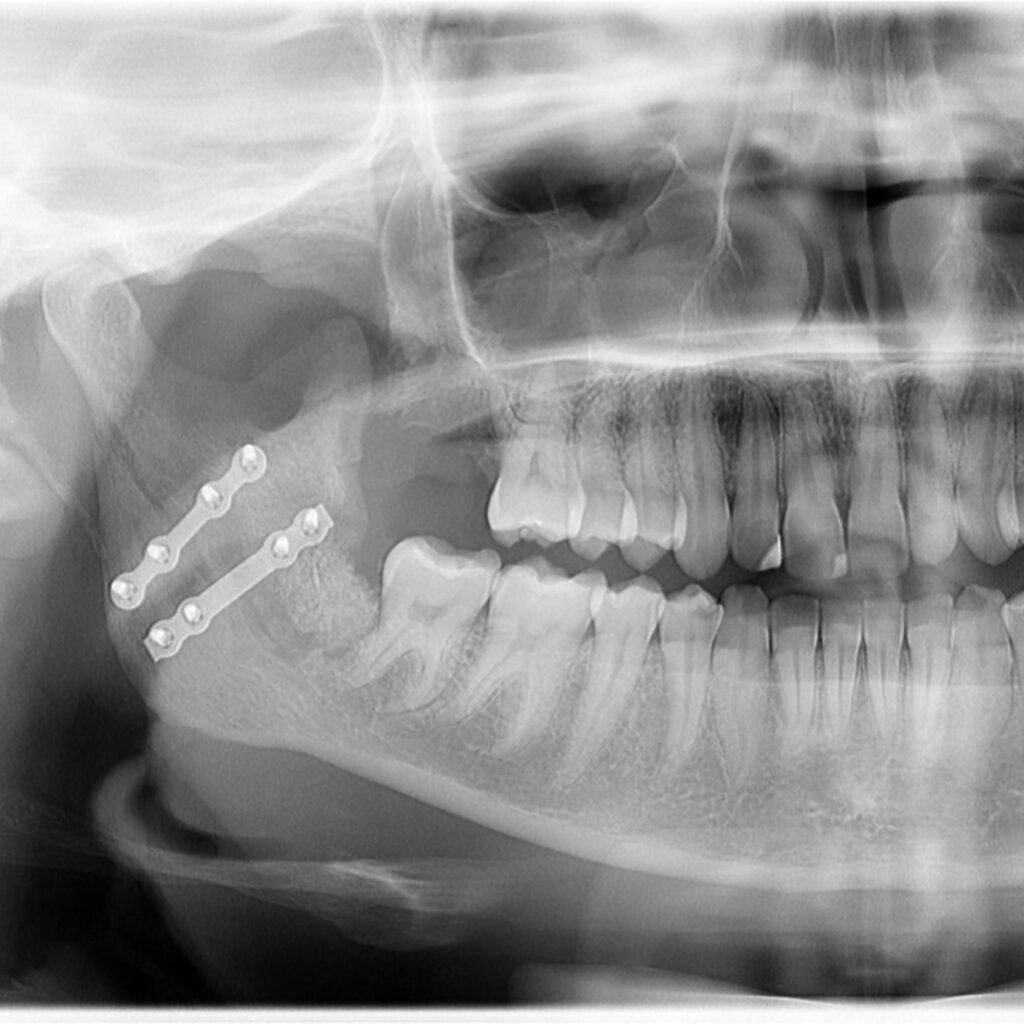

A Patologia Oral e Maxilofacial é a especialidade responsável pelo diagnóstico e tratamento de doenças que afetam a boca, mandíbula e estruturas faciais. Atua na identificação de lesões, cistos e tumores, garantindo diagnóstico preciso e tratamento adequado para preservar a saúde bucal e geral do paciente.